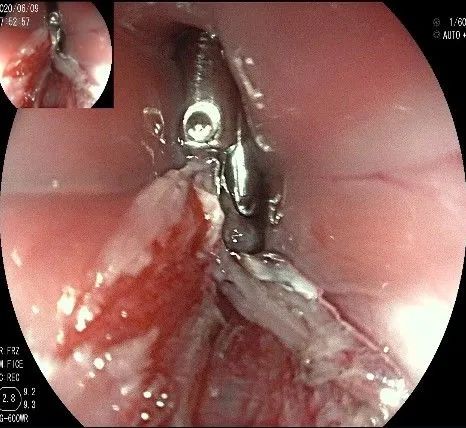

此时瘤体基底部已暴露出来,起源于固有肌层。

这是最后的“根”部。

换用IT刀可以轻松剥离,又避免切入过深造成穿孔。

剥离接近完成,最后连接的薄层组织。

瘤子完整切除,随透明帽吸出的时候脱落到左侧会厌部,当时我们团队的麻醉、护理等人员都捏了一把汗,因为是静脉全麻没有插管,离声门太近了,一不小心进入气道会形成气管异物,造成严重后果!迅速换用鳄齿钳钳夹牢固,顺利取出!